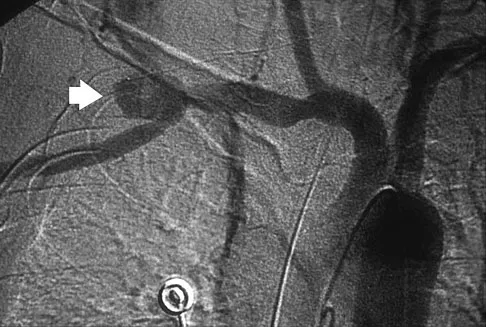

Question 61

A 16-year-old football player sustains a direct blow to the anterior aspect of his flexed right knee. Examination reveals a contusion over the anterior tibial tubercle and a small effusion. MRI scans are shown in Figures 33a through 33c. What is the most likely diagnosis?

Explanation

The MRI scans show disruption of the fibers of the PCL. Patients sustaining an isolated acute PCL injury can present with only minimal discomfort and have full range of motion. When examination reveals a contusion over the tibial tubercle and discomfort with the posterior drawer examination, with or without instability, a possible injury to the PCL should be considered. In acute injuries, the reported accuracy of MRI imaging for diagnosing PCL tears ranges from 96% to 100%. Resnick D, Kang HS: Internal Derangement of Joints: Emphasis on MRI Imaging. Philadelphia, PA, WB Saunders, 1997, pp 699-700. Harner CD, Hoher J: Evaluation and treatment of posterior cruciate ligament injuries. Am J Sports Med 1998;26:471-482.